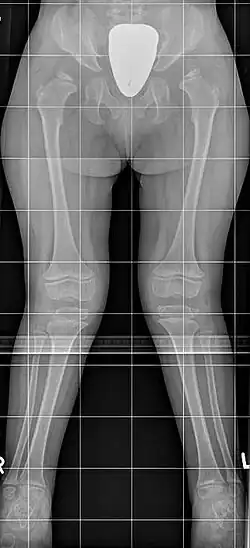

Die Schwere der Erkrankung ist sehr unterschiedlich, die Erkrankten des Typ B sind meist weniger stark betroffen. Es ist durchaus möglich, dass die Erkrankung wegen fehlender Beschwerden erst im Erwachsenenalter diagnostiziert wird, andere Patienten haben bereits als Kleinkinder deutliche körperliche Anzeichen. Typisch ist ein Kleinwuchs mit kurzem Hals und typischer Gesichtsform, sowie eine Hornhauttrübung und X-Beine, es besteht keine Intelligenzminderung und keine Vergrößerung von Milz oder Leber. Im Einzelnen finden sich:

- Äußere Erscheinung: Typisch sind eine Kielbrust (Pectus carinatus; seltener eine Trichterbrust), eine Gelenk-Überbeweglichkeit (Hypermobilität) und X-Beine (Genua valga). Der Hals ist meist kurz. Das Gesicht zeigt typische Veränderungen, die an Wasserspeierfiguren (Gargoylen) an gotischen Kirchen erinnern und daher oft als Gargoylismus bezeichnet werden: Das Kinn ist vergrößert und vorstehend, das Gesicht vergröbert mit ausgeprägten Wangen bei großem Kopf (Makrozephalie).

- Wirbelsäule: Die Knochenveränderungen an der Wirbelsäule (spondyläre Dysplasie) sind so typisch, dass ein Röntgenbild häufig zur Diagnosestellung führt. Die Wirbelkörper sind flacher (Platyspondylie), vor allem die Wirbel am Übergang zwischen Brust- und Lendenwirbelsäule sind oft keilförmig mit daraus folgender Bildung eines Gibbus. Weiter besteht eine knöcherne Anlagestörung mit einem zu kleinen und nicht ausreichend fixierten Dens axis (des Zahnfortsatzes des zweiten Halswirbelkörpers), wodurch die Gefahr einer (atlantoaxialen) Instabilität besteht. Dies kann zu einer Spinalkanalstenose bis hin zur Querschnittsymptomatik führen. Eine Gefahr besteht besonders bei der endotrachealen Intubation im Rahmen einer Vollnarkose. Eine Rückenmarkkompression kann sich aber sowohl am Hals-Kopf-Übergang (atlantooccipital) als auch am Übergang zwischen Brust- und Lendenwirbelsäule (throrakolumbal) schleichend mit zunehmender Ermüdbarkeit und reduzierter Gehstrecke entwickeln. Am Becken besteht eine Hypoplasie des unteren Anteils des Os ilium sowie meist eine epiphysäre Dysplasie des Oberschenkelkopfes (Femurkopf-Epiphyse), die im Röntgenbild oft an einen Morbus Perthes erinnert. Es besteht meist eine Coxa valga. Die Mittelfußknochen (Ossa metatarsalia) sind körpernah zugespitzt, alle langen Röhrenknochen verkürzt.